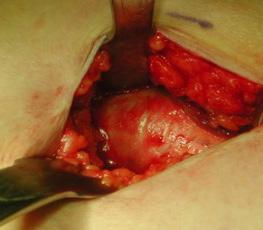

Manejo ortopédico de la artropatía hemofílica en México. Por: Dr. Armando R. Hernández Salgado, Ortopedista y Traumatólogo, Cirujano de Artroscopia y Cirugía de Rodilla, Especialista en Artropatía Hemofílica, Asesor Voluntario de FHRM. Pág. 109